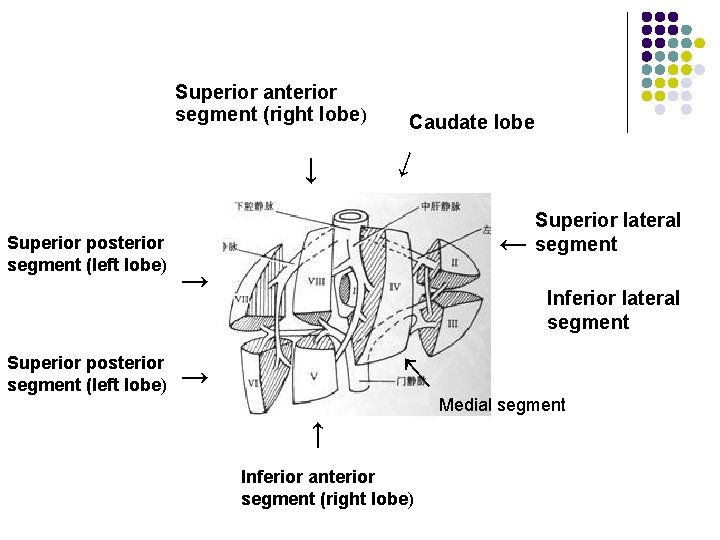

Superior anterior segment (right lobe) → → Superior lateral segment → Inferior lateral segment → Medial segment → Superior posterior segment (left lobe) → → Superior posterior segment (left lobe) Caudate lobe Inferior anterior segment (right lobe)